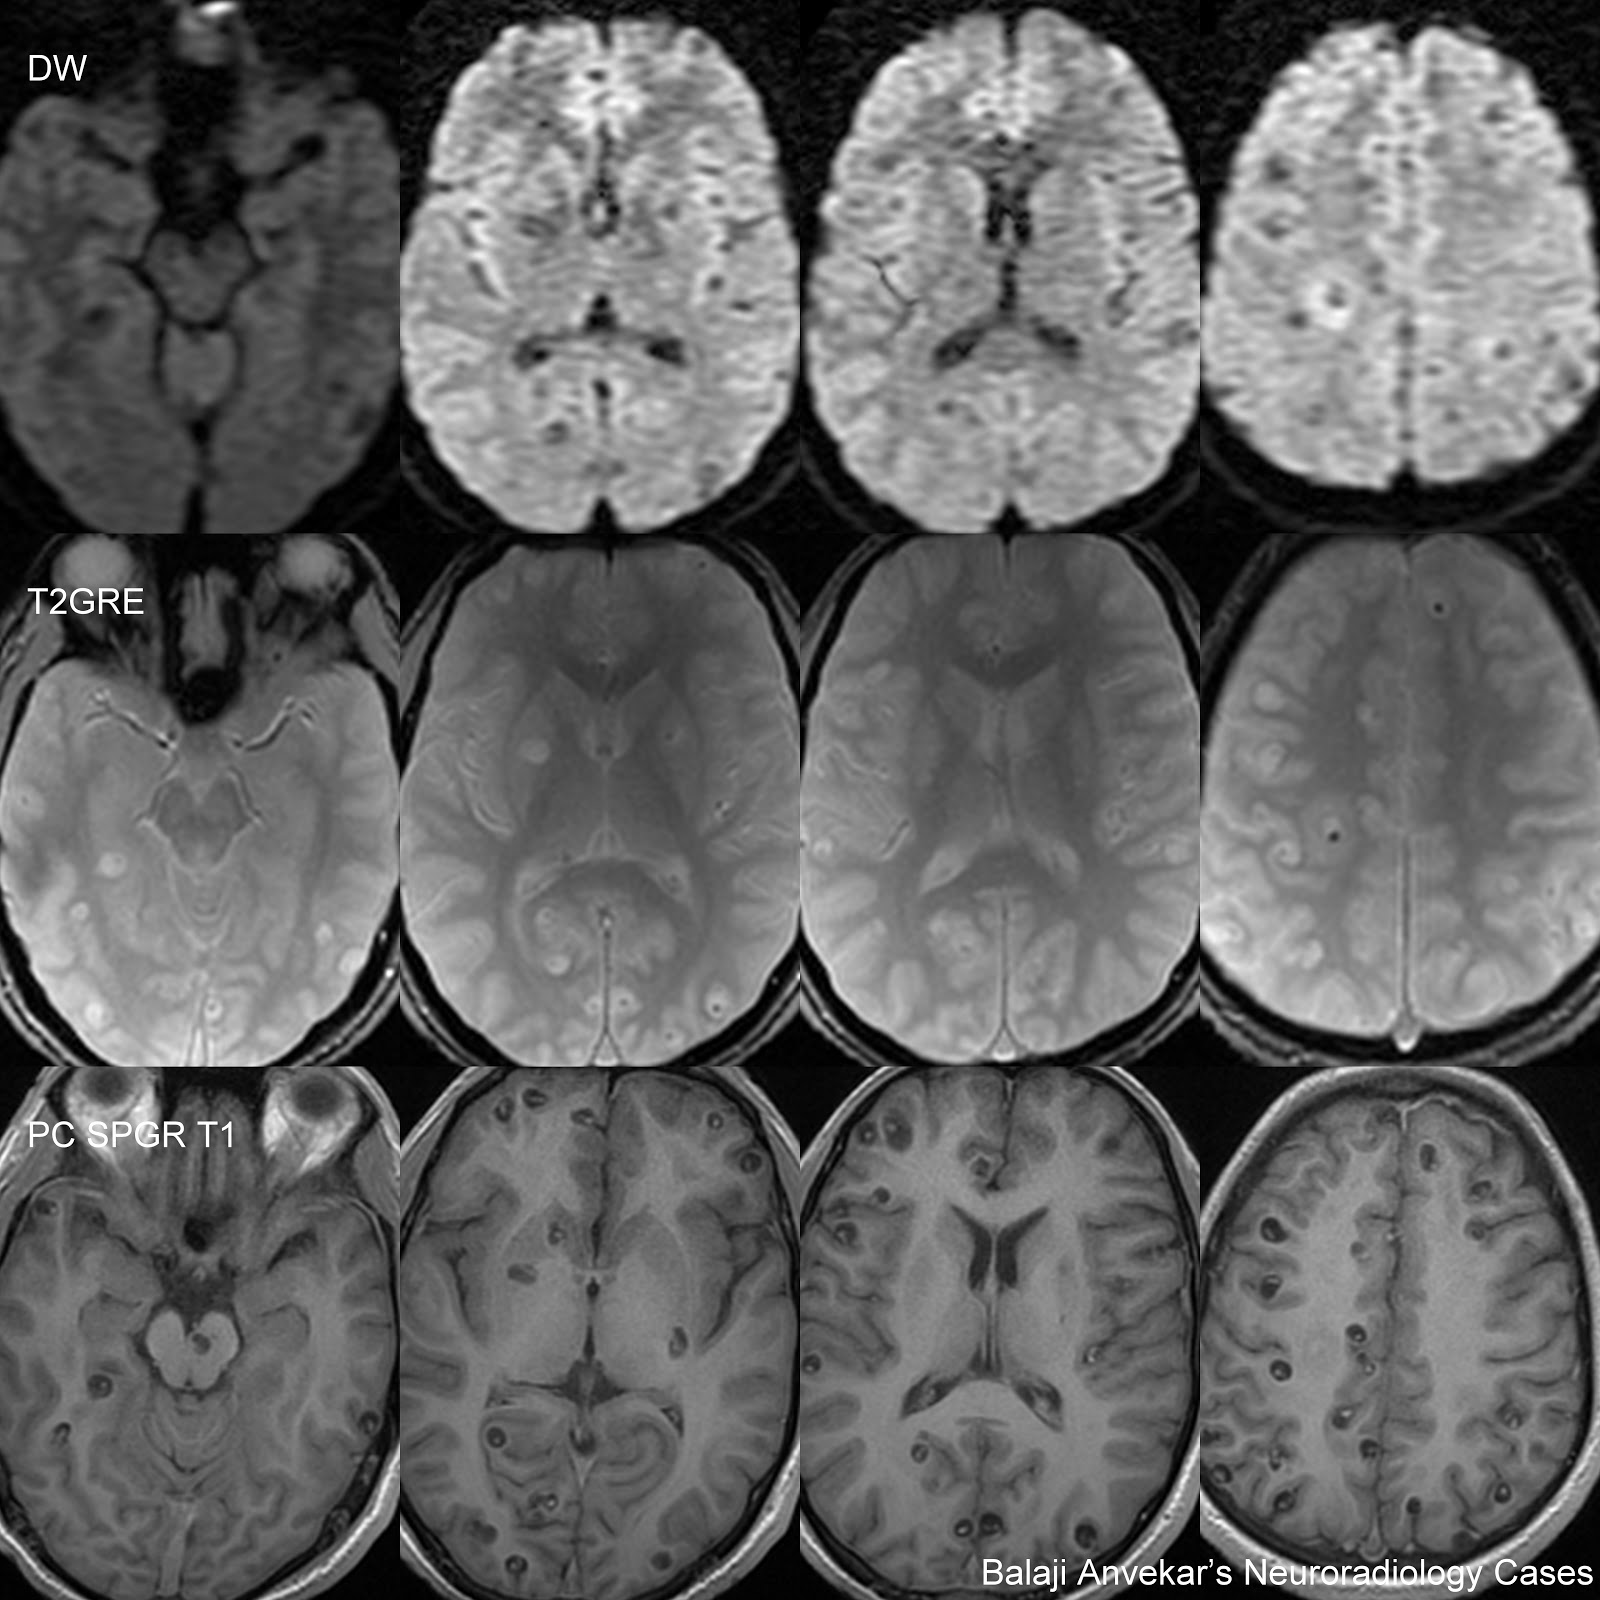

Нейроцистицеркоз и эхинококкоз что это такое - фото презентация